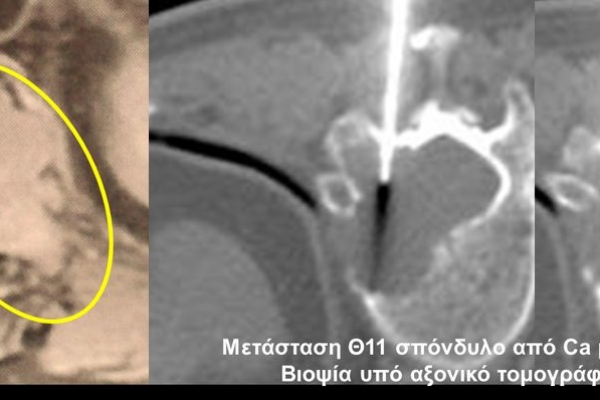

Η οστική βιοψία και η βιοψία όγκων μαλακών μορίων χρησιμοποιείται για την ιστολογική διάγνωση αλλοιώσεων (καλοήθων - κακοήθων / πρωτοπαθών ή μεταστατικών) ή για τη λήψη υλικού προς καλλιέργεια ώστε να αναδειχθεί το μικρόβιο που προκαλεί τη λοίμωξη του μυοσκελετικού συστηματος (πχ σπονδυλοδισκίτιδα). Η βιοψία υπό συνεχή απεικονιστική καθοδήγηση συμβάλλει στην υψηλή ακρίβεια τοποθέτησης της βελόνης εντός της βλάβης με ασφαλή προσπέλαση. Η χρήση σύγχρονων ομοαξονικών συστημάτων βιοψίας (coaxialtechnique) επιτρέπει την λήψη πολλαπλών δειγμάτων με μια μόνο παρακέντηση.